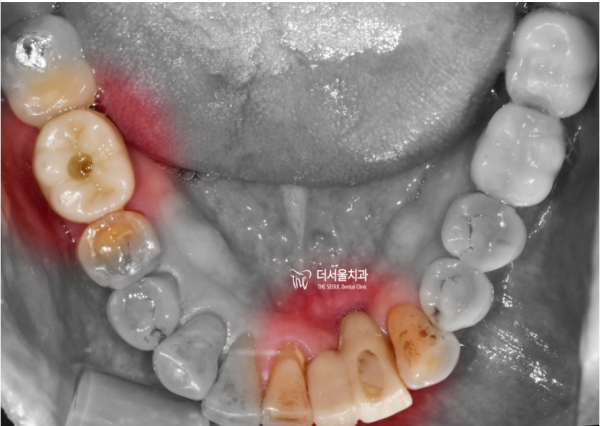

구강내 사진을 보면, 잇몸이 아래로 많이

내려가 있는 것을 확인할 수 있습니다.

환자분께서는 브릿지는 싫다고 하셨기 때문에

뼈 이식 후 앞니 임플란트를 해 드리도록 하였습니다.

If you look at the picture in the mouth, the gums go down a lot

You can see that it's down.

She said she didn't like the bridge part

After the bone transplant, we will give you an implant for your front teeth implant.